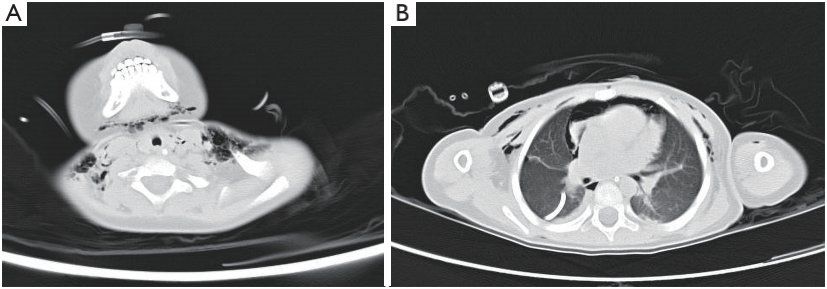

术后第3天,CT显示两侧有少量气胸和部分肺不张,颈部、纵隔和胸壁有皮下气肿(图3A、3B)。胸腔闭式引流术后第3天取下引流管,24小时内不抽气。

图3. CT显示少量气胸、皮下气肿、纵隔气肿和右胸引流管。CT、计算机断层扫描